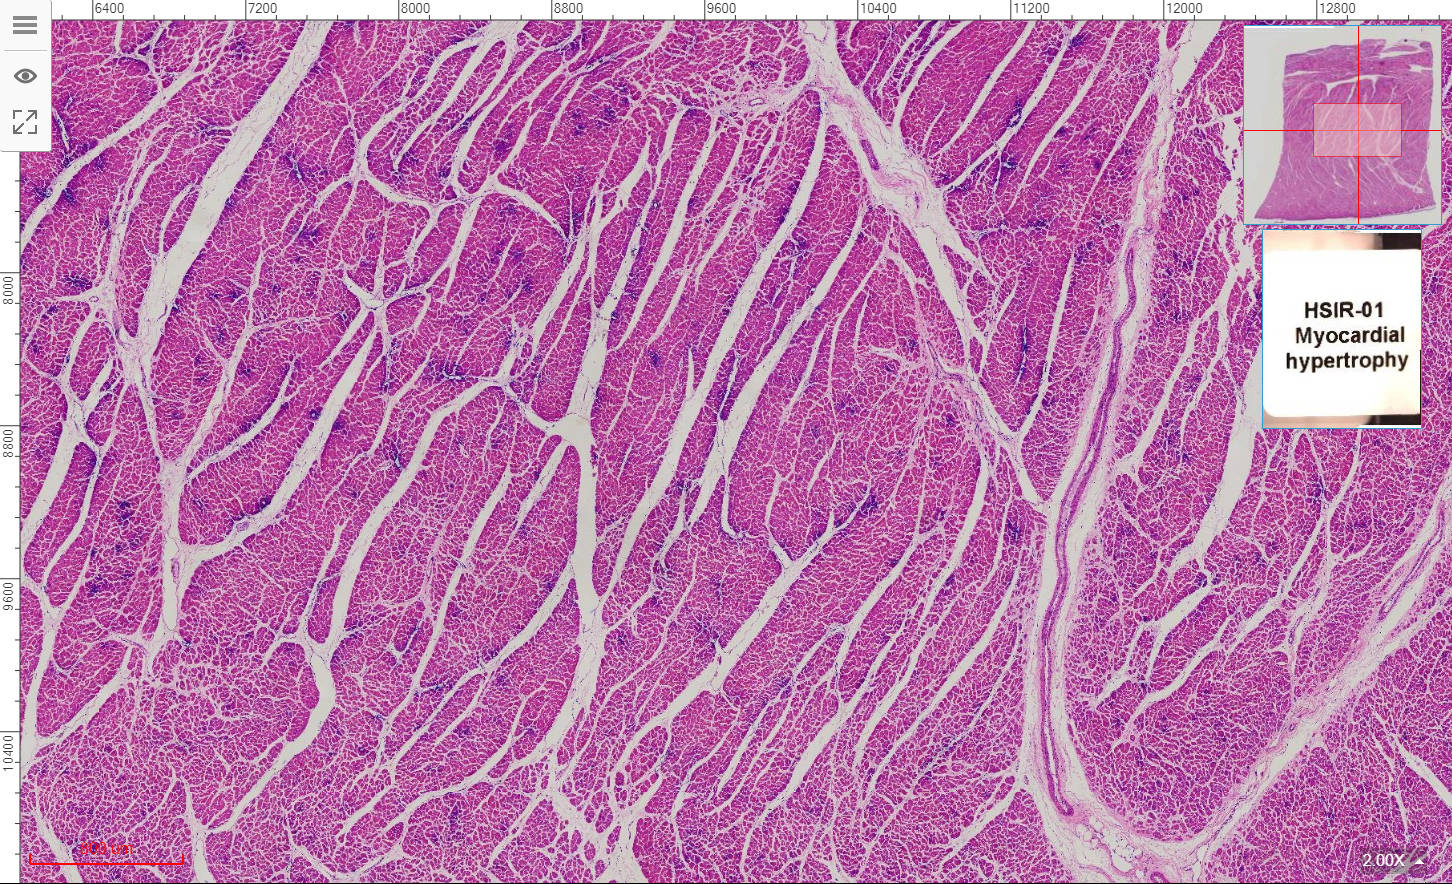

1, Injury and repair of cell and tissue

HSIR-01 Myocardial hypertrophy